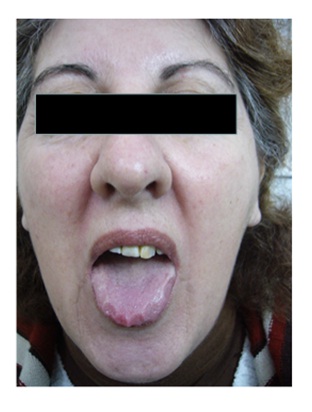

Los signos frecuentes se presentan en la Tabla 6. La figura 3, La figura 4, La figura 5 y La figura 6 describen los hallazgos de importancia en el examen de cuello y de la orofaringe, que habitualmente son escasamente destacados en la enseñanza de la semiología. La circunferencia de cuello fue de 45,9 ± 3,9cm en hombres (normal hasta 42) y 41,8 ± 3,7cm en mujeres (normal hasta 38). El espacio crico-mental se evaluó cualitativamente15. En el examen de la orofaringe, se evaluaron los grados de Mallampati16, como predictores de severidad de apneas del sueño. Los grados más altos se asociaron a IAH mayores, aunque en forma no significativa (Figura 7).

Figura 7: Grados de Mallampati y severidad de apneas del sueño (IAH). El examen de la orofaringe durante la apertura bucal y protrusión de la lengua (sin fonación) permite evaluar globalmente las estructuras anatómicas. Grado I: paladar blando, úvula, istmo de las fauces, pilares anteriores y posteriores visibles. Grado II: paladar blando, parte de la úvula e istmo de las fauces visibles. Grado III: paladar blando y sólo base de la úvula visibles. Grado IV: solamente es visible el paladar duro.

De las enfermedades endócrinas predisponentes para apneas obstructivas del sueño se estudiaron el hipotiroidismo y la acromegalia. Se estudió una serie consecutiva de pacientes con acromegalia27, consistente de nueve hombres y nueve mujeres portadores de clínica de acromegalia con somatomedina C (IGF-1) aumentado y nadir de hormona de crecimiento (GH) > 1 ng/ml, post sobrecarga de glucosa. La remisión luego del tratamiento se definió como IGF-1 normal, con nadir de GH < 1 ng/ml. Los tumores hipofisarios fueron predominantemente macro-adenomas. El tamaño tumoral fue de 15,2 ± 10,9 mm. La mediana de la edad al diagnóstico de acromegalia fue de 52,7 (27 a 71) años. El tiempo de evolución al diagnóstico polisomnográfico fue de 8,7 ± 8,2 años. La remisión se demostró en 4 pacientes, 12 estaban en actividad y 2 se perdieron en el seguimiento. El ronquido y las apneas observados fueron síntomas comunes. La somnolencia diurna no fue un hallazgo relevante (Epworth = 6,8 ± 4,7). Los hallazgos del examen físico fueron: macroglosia, signo de Mallampati grado 3,1 ± 1,3, y estrechamiento lateral de la faringe grado 2,4 ± 0,7. La circunferencia de cuello fue de 41,3 ± 4,7cm. Se diagnosticó apneas del sueño de tipo obstructivo en 17 pacientes, con los siguientes hallazgos polisomnográficos: IAH = 27,0 ± 25,2; IDO = 15,3 ± 16,8; Tiempo en Hipoxia = 31,4 ± 33,2%; Eficiencia del sueño = 71,6 ± 16,6%; Estadio N1 = 27,3 ± 19,3%; Estadio N2 = 36,7 ± 9,7%; Estadio N3 = 23,4 ± 13,0% y Estadio R = 11,9 ± 8,0%.